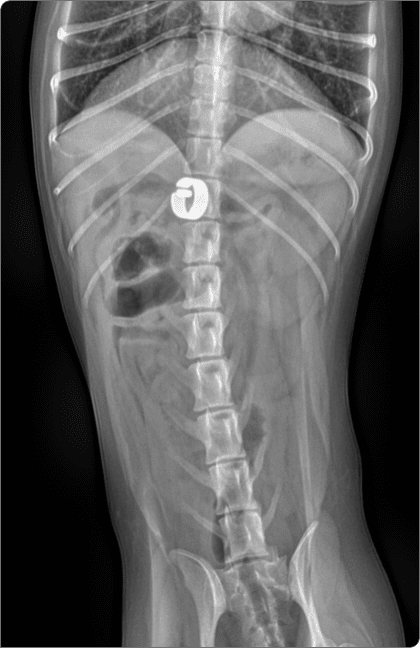

CT·심초음파 등 정밀 영상검사로 혈관 구조를 평가하고 수술 계획을 수립하며,

CT 혈관조영, 심장초음파 등 고사양 영상장비를 활용하여

혈관 구조와 병변을 정밀 분석, 최적의 수술 계획을 수립

동맥관은 출생 후 닫혀야 하지만, 열려 있는 상태를

동맥관 개존증(PDA)이라고 함.

이로 인해 폐동맥 고혈압과 심장 과부하가 발생할 수 있으며,

조기 수술 교정 시 증상 개선과 장기 예후가 가능.